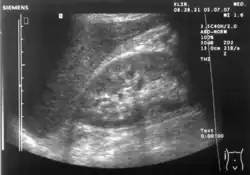

Échographie rénale

L'échographie des reins est essentielle dans le diagnostic et la prise en charge des maladies rénales. Les reins sont facilement examinés et la plupart des modifications pathologiques des reins se distinguent par échographie[9].